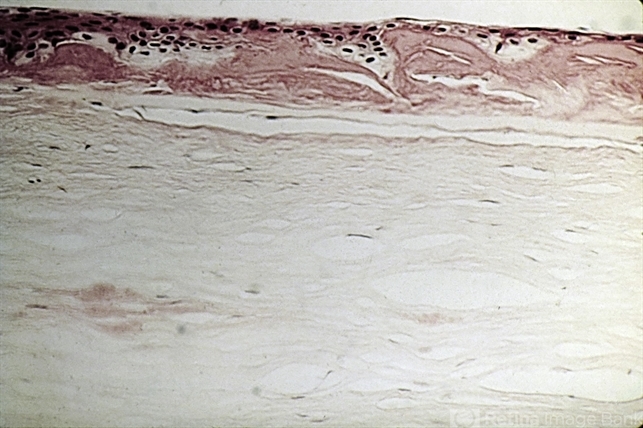

- lattice dystrophy, stroma

- On routine hematoxylin and eosin stained sections, the lesions of lattice dystrophy are pinker than the surrounding stroma and are fusiform in shape.